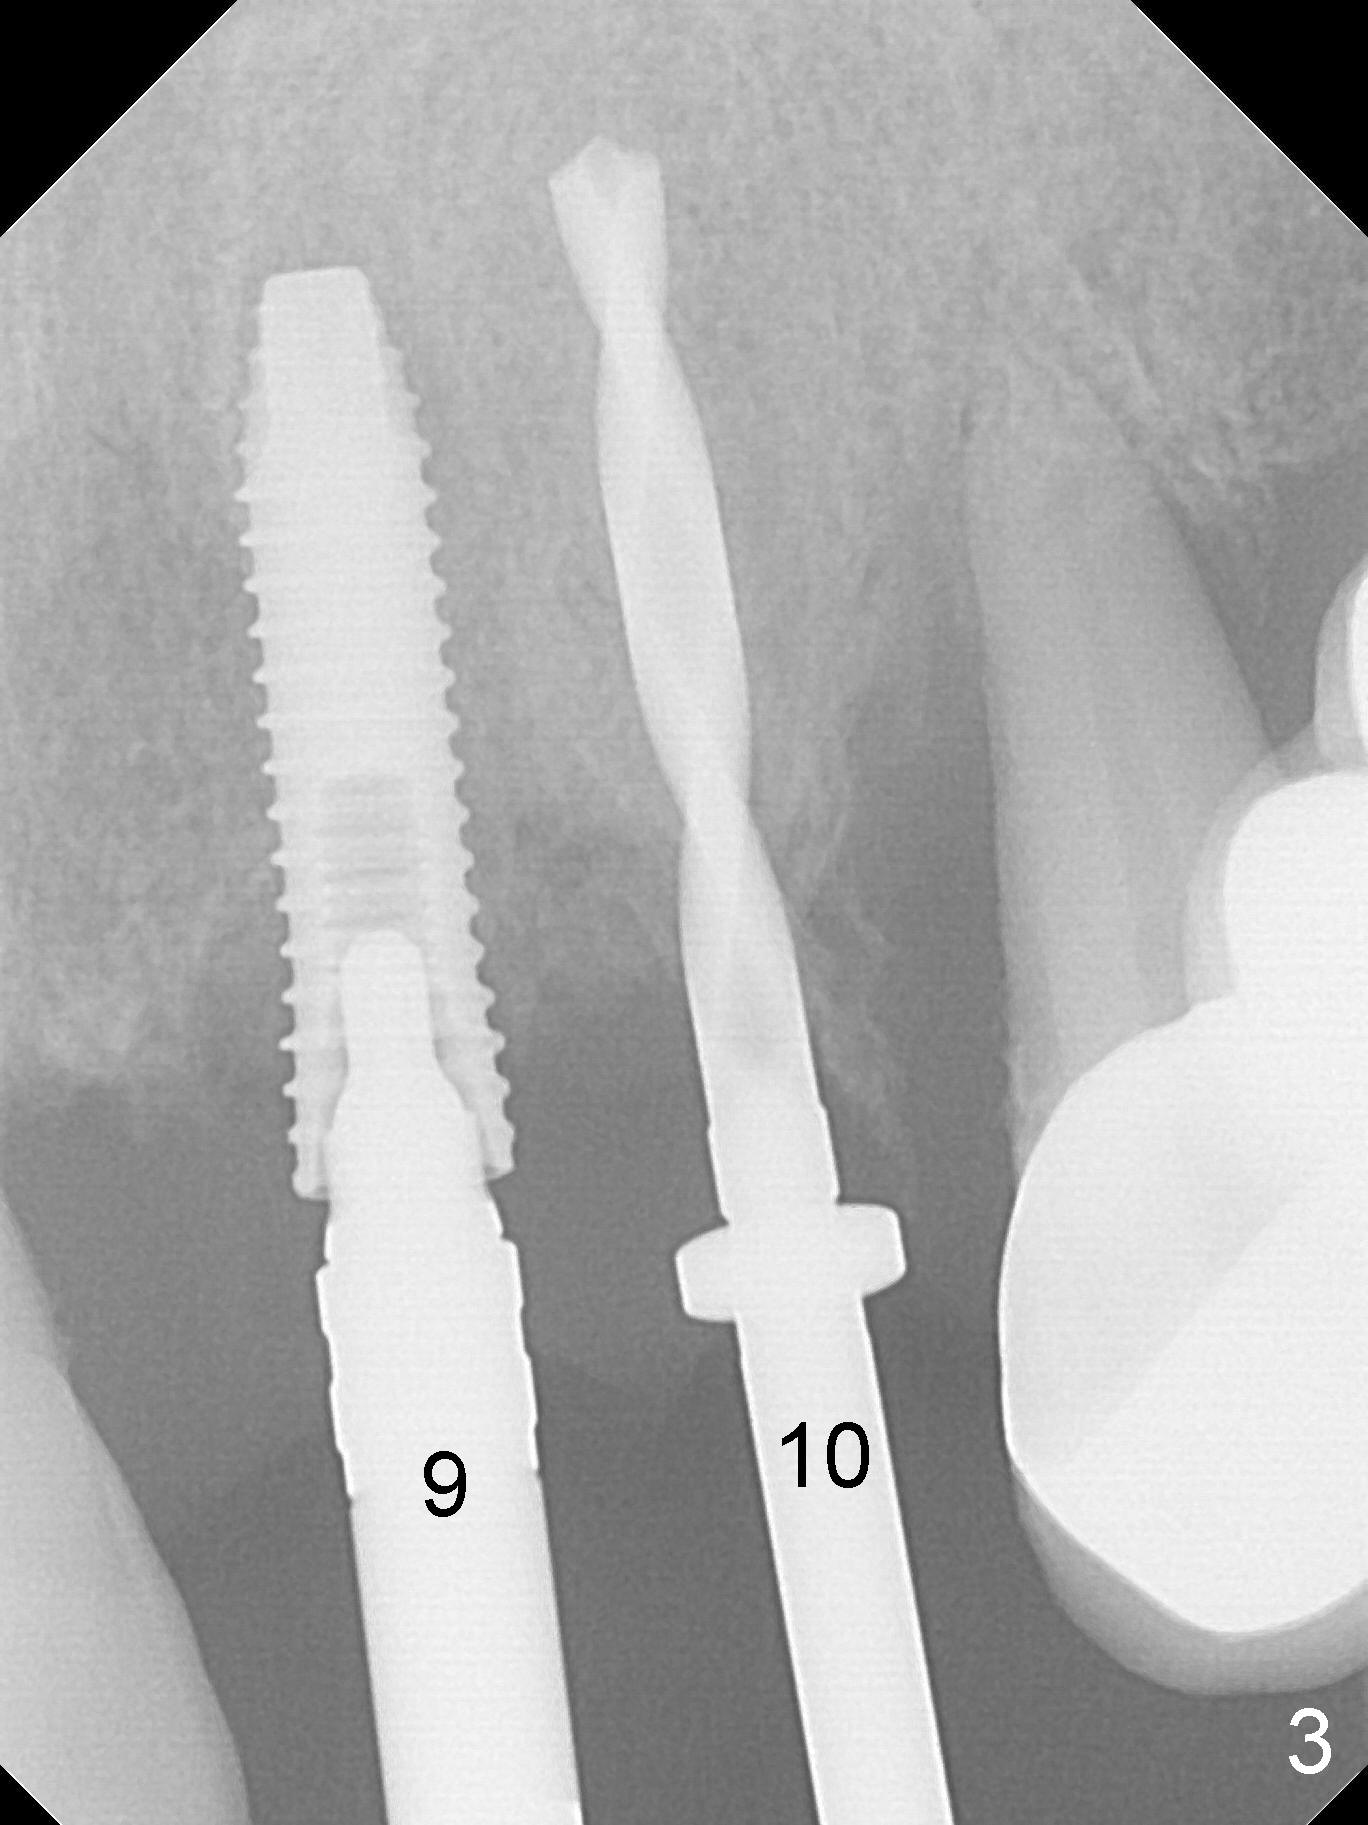

The dentition is poor except #6 and 8 (Fig.1). The gingiva is erythematous at #9-11 (Fig.2). The teeth #9 and 10 are extracted first; a 4x16 mm UF implant is placed at #9, while a 2 mm pilot drill is at the site of #10 (Fig.3). The implant at #9 is placed deeper with placement of 4.5x5.5(5) mm abutment; a 3.8x15 mm implant is placed at #10 initially (Fig.4). While the latter is placed deeper, a 4x16 mm implant is placed at #11 (Fig.5 after removal of #11-15 FPD (fixed partial denture)). In fact the trajectory at #11 is not difficult to be changed with 2 mm drill (Fig.6). After use of 3 mm drill, the implant is reinserted at #11 with ideal trajectory (Fig.7). After further seating of the implant at #11, graft is placed in the remaining sockets of #9-11 (Fig.8 *; later more graft is placed mesial to #11 implant (^)). Finally, a 4.5x7(5), 4.5x15° B (4) and 5.5x7(5) mm abutments are tightened and prepared (Fig.9) for splinted provisional at #9-10.